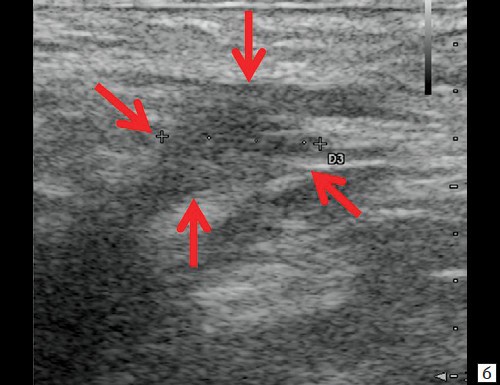

При контрольном УЗ-исследовании через 14 дней после оперативного вмешательства: описываемое гипоэхогенное жидкостное образование с четкими неровными контурами уменьшилось в размере до 1,1×0,6×0,8 см и объеме до 0,29 мл (рис. 3, а, б). Сосудистая реакция в подкожно-жировой клетчатке не определяется (рис. 3, в). Свищевой ход визуализируется нечетко, уменьшился в размере до 0,8×0,2×0,4 см (рис. 3, г).

Рис. 3. а, б – В-режим. Через 14 дней после оперативного вмешательства. Гипоэхогенное жидкостное образование с четкими неровными контурами в перианальной области уменьшилось в размерах до 1,1×0,6×0,8 см, объемом 0,29 мл (стрелки);

г, д – В-режим. Через 14 дней после оперативного вмешательства. Свищевой ход визуализируется нечетко, уменьшился в размере до 0,8×0,2×0,4 см (стрелки).